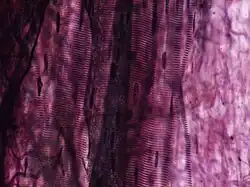

Forma enlaces catiónicos, aniónicos y no iónicos con la elastina, el constituyente principal del tejido elástico fibroso.[2] La elastina tiene una afinidad fuerte por el complejo hierro-hematoxilina formado por los reactivos en la tinción y por lo tanto la retendrá mucho más tiempo que otros componentes del tejido, por lo que aparecerá teñida, mientras los otros elementos aparecen poco coloreados. El uso de tiosulfato de sodio remueve el exceso de iodo y se utiliza una contratinción (mayoritariamente tinción de Van Gieson) para dar contraste a la tinción principal. Las fibras elásticas y los núcleos celulares se tiñen de negro, las fibras de colágeno de rojo y otros elementos del tejido incluyendo el citoplasma se tiñen de amarillo.